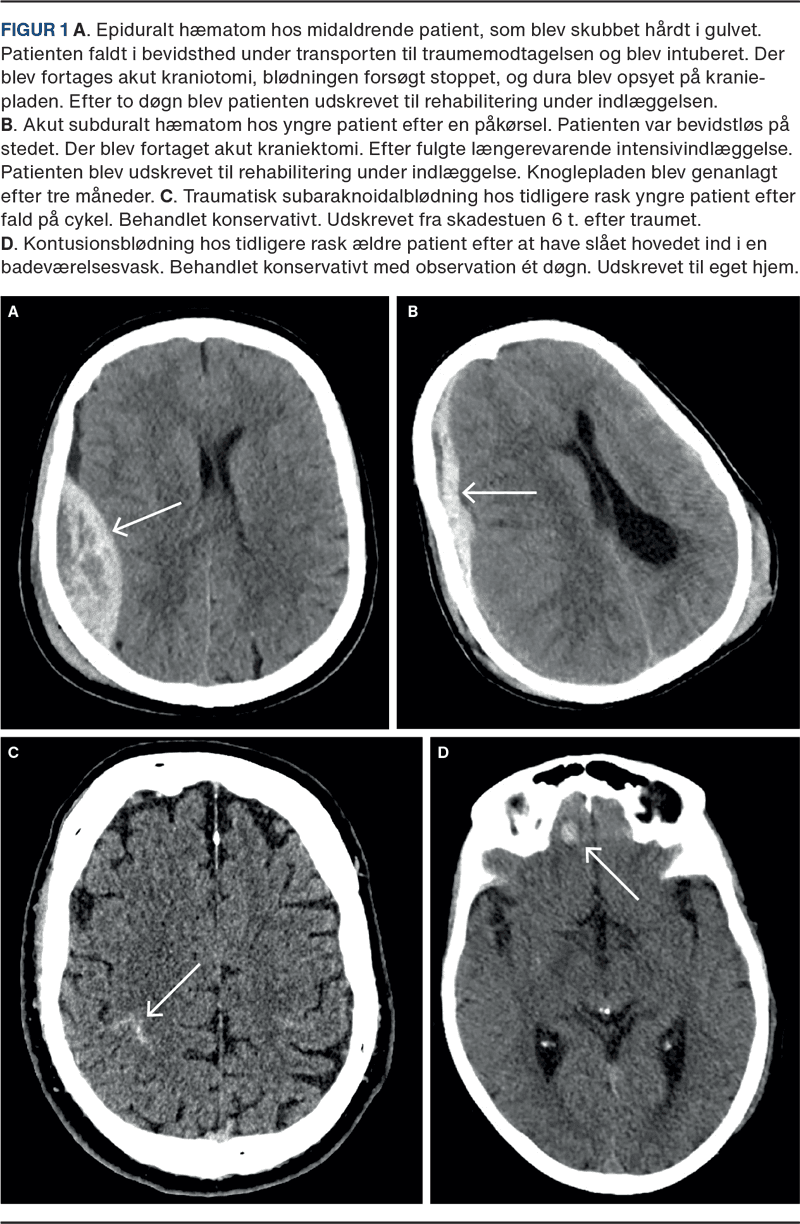

Ved epiduralt hæmatom (EDH) ligger blødningen mellem dura og kraniet og afgrænses af kraniets suturer, hvilket giver det karakteristiske linseformede udseende på billeddiagnostik (Figur 1 A). Den kan være arteriel eller venøs og ses ofte i forbindelse med kraniebrud, typisk temporalt, hvor kraniet er tyndest. Arterielle blødninger skyldes skade på meningeale arterier, mens venøse opstår som sivblødning fra knoglens vener [1, 4]. Klinisk ses ofte et stumpt hovedtraume mod temporalregionen. Patienten kan være kortvarigt bevidstløs, vågne op med symptomfri periode (lucid interval) og derefter få neurologisk forværring, da tiltagende hæmatom kan medføre, at dura løsrives fra kraniet, hvilket medfører en drastisk masseeffekt [4].

Ved akut subduralt hæmatom (aSDH) er blødningen lokaliseret mellem dura mater og arachnoidea og følger kraniets inderside, hvilket giver den karakteristiske halvmåneform på billeddiagnostik (Figur 1 B). Men aSDH kan også strække sig langs falx cerebri og tentorium cerebelli. Ved højenergitraumer skyldes blødningen hyppigst ruptur af en arterie, hvilket ofte vil føre til bevidsthedspåvirkning, sommetider forudgået af lateraliserede udfald. Patienter med øget subduralt rum som følge af hjerneatrofi eller shuntbehandling er mere udsatte for venøse blødninger fra brovener. Disse kan manifestere sig som aSDH, men opdages ofte først uger senere som kSDH [1, 3, 5]. Derfor ses aSDH hos yngre patienter typisk efter et større stumpt traume, mens ældre, alkoholikere eller shuntbehandlede kan udvikle aSDH efter lavenergitraumer, f.eks. fald fra egen højde [5].

Traumatisk subaraknoidal blødning (tSAH) forekommer i subaraknoidalrummet, ofte langs kraniets konveksitet (Figur 1 C). Selv små traumer kan medføre tSAH, sandsynligvis på grund af brist af små skrøbelige vener, men mekanismen er ikke fuldt klarlagt [7]. Isoleret tSAH har som regel et mildt forløb, og mange tilfælde opdages ikke, da patienterne ofte er ved fuld bevidsthed. Risikoen for neurologisk forværring er lav, og indlæggelse kan undlades hos ellers raske, upåvirkede patienter [7, 8].

Denne blødningstype kaldes også traumatisk intracerebral blødning. Den opstår ved hurtig deceleration, hvor hjernen kolliderer med kraniets inderside, hvilket skader parenkym og små blodkar. Blødningen kan forekomme ved slagstedet (coup) eller modsatte side (contre-coup) (Figur 1 D), typisk hvor kraniets inderside er irregulær, f.eks. fossa anterior eller temporalpolen. Skade på blod-hjerne-barrieren kan medføre vasogent ødem, hvilket klinisk også kan give et symptomfrit interval. Ødemet udvikles mest inden for 24 t., og sekundært cytotoksisk ødem kan opstå over 7-14 dage [1, 6]. Patienter med kontusionsblødning har størst risiko for neurologisk forværring det første døgn, men kan opleve hovedpine, kvalme og opkast i op til to uger efter traumet [6].